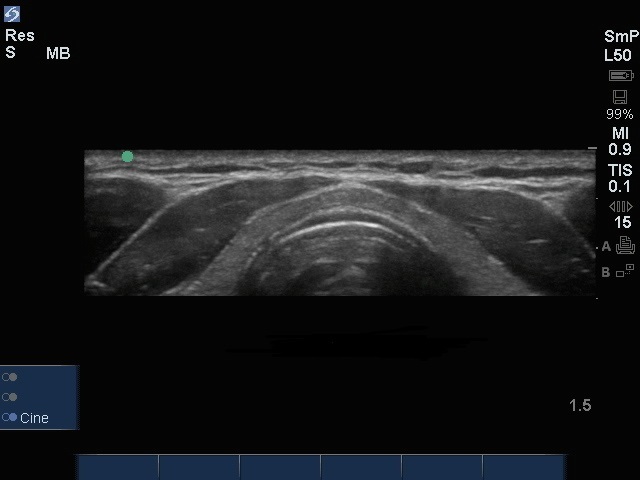

甲状腺峡图像